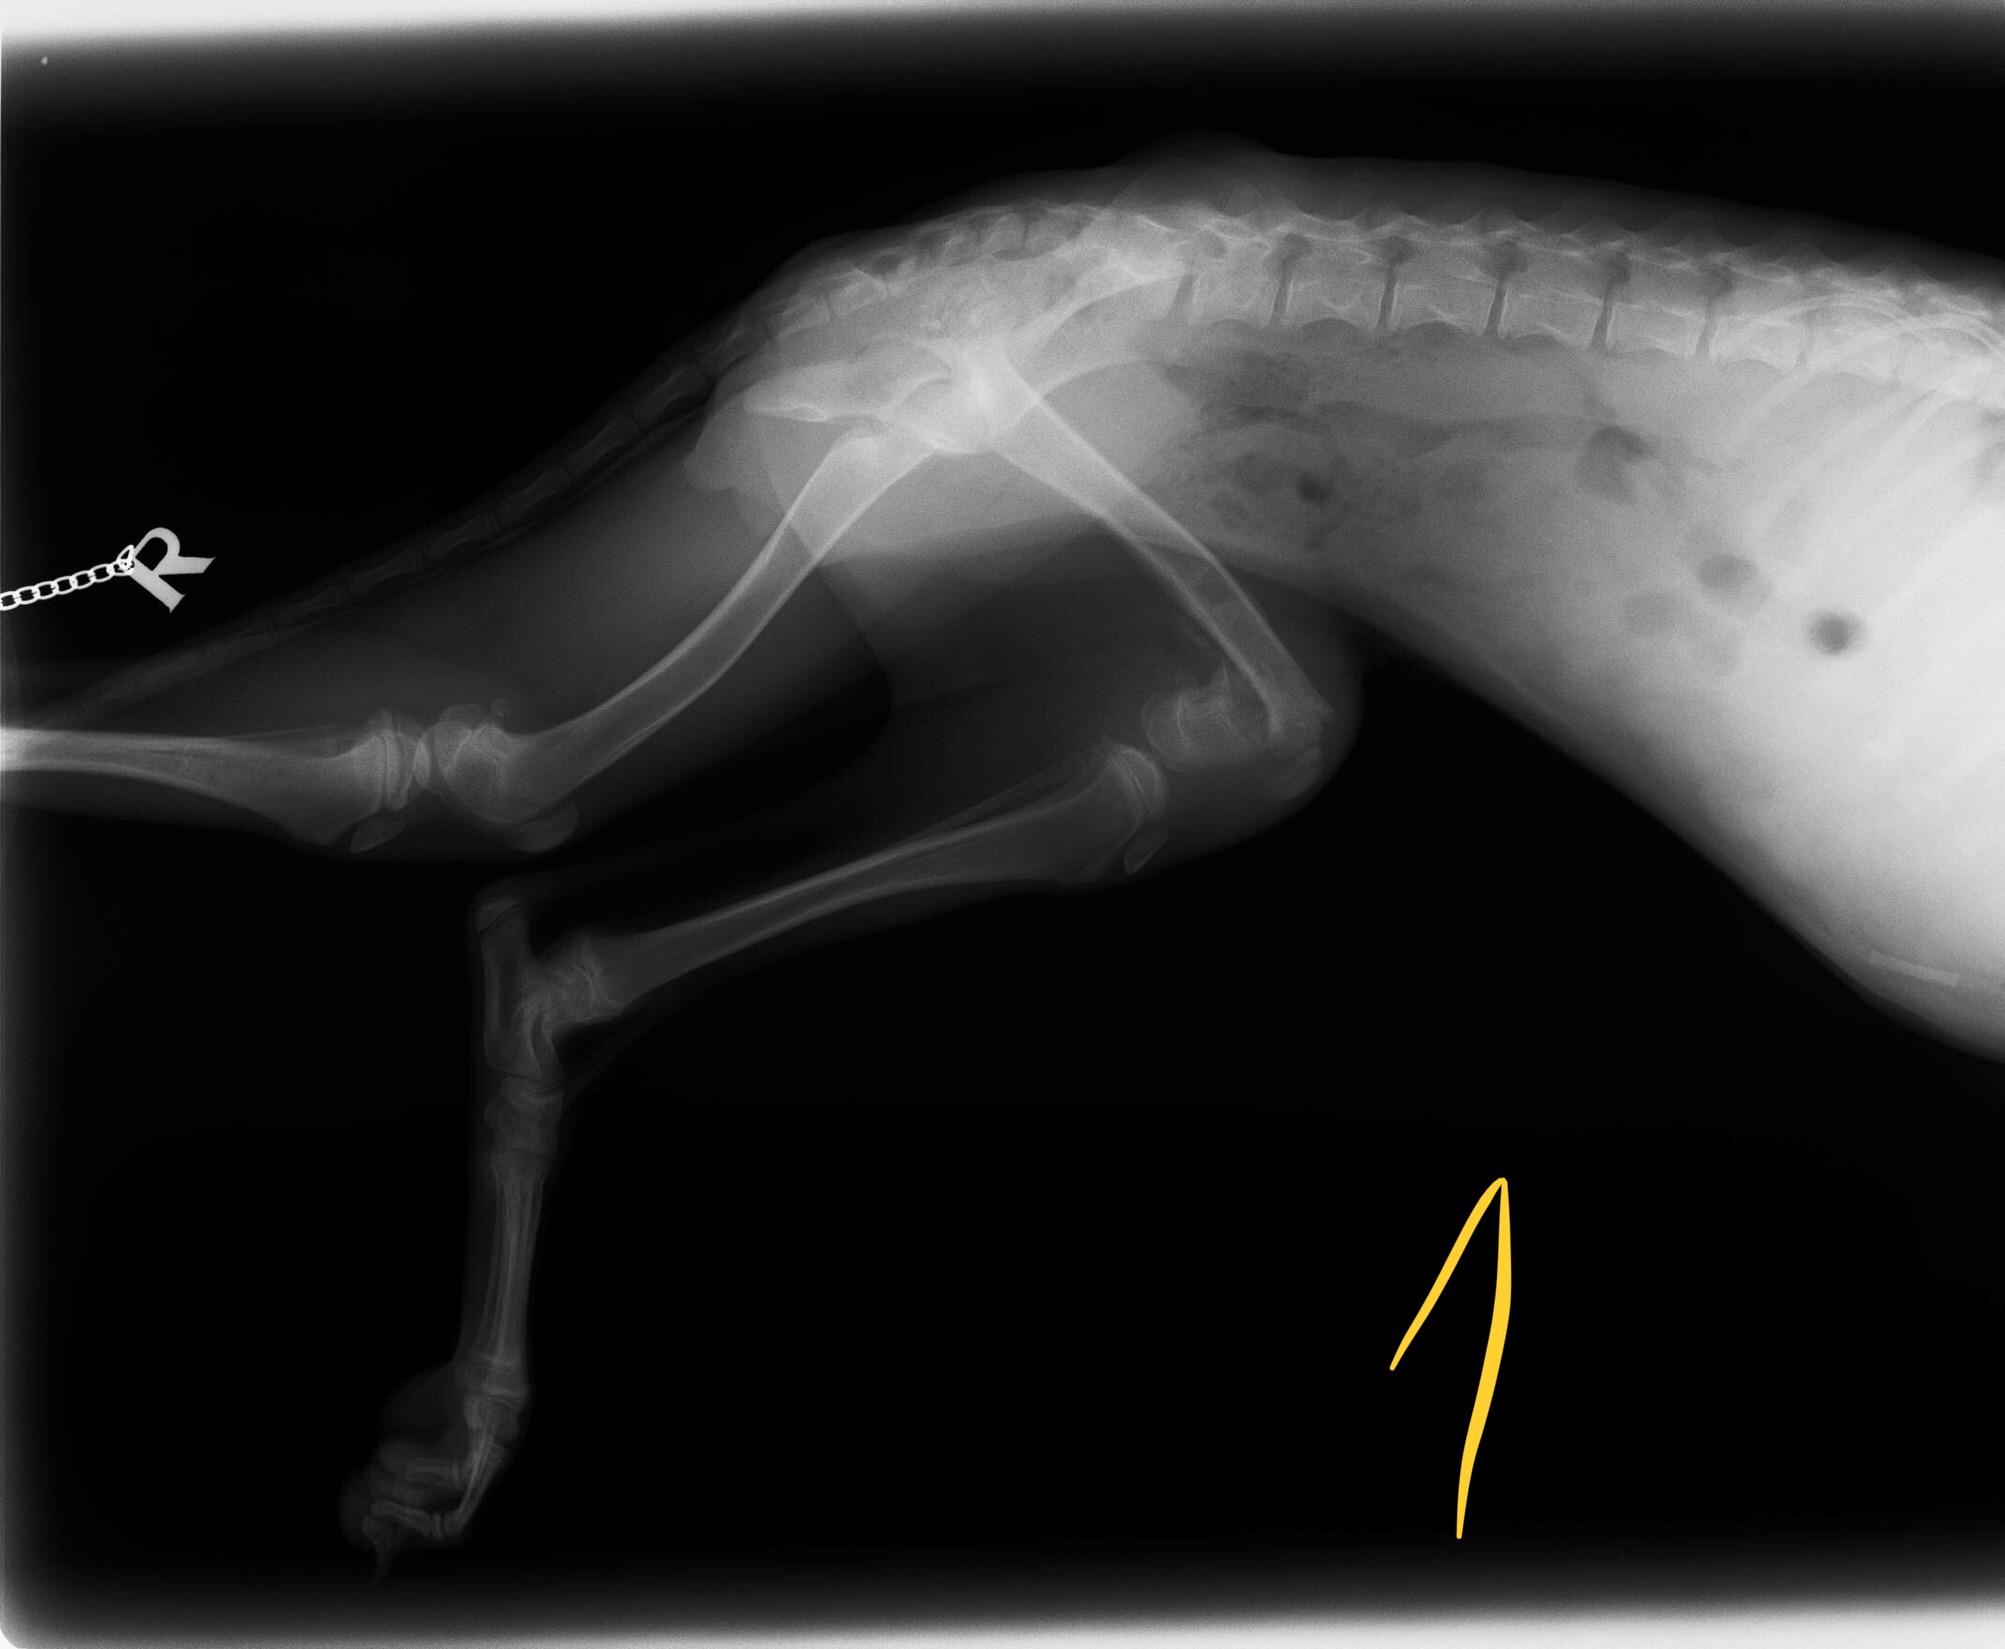

HEALTHSHARE My vet said Ella needs her back left leg amputated since the 1st operation she had was not successful. She can walk and run with a slight limp. She had the operation when she was a puppy 4/5 mi this old. Now she is 11 months old. Photo 1 pre op. Photo 2 after op. What do you think. Kind regards Pet's info: Dog | Mixed Breed Medium (23 - 60lb) | Female | spayed | 11 months and 22 days old | 38 lbs Location: United Kingdom

Thank you for reposting your question with pictures. The second x-ray is a little dark and is difficult to read, but I can certainly see that the area is not normal and why your vet would recommend amputation since the area will not get any better. However, if Ella only has a slightly limp, then I'm not sure why the amputation needs to happen now. Some dogs do very well with an abnormal leg for many years. If at some point it starts causing her more problems, it can always be amputated at that time. And certainly only having 3 legs puts more strain on the other legs, so we try to wait to amputate unless the leg is currently painful or causing problems. Good luck! I hope that was helpful and answered your question. Thanks for using Petco Pet Education Center, formerly Petcoach.